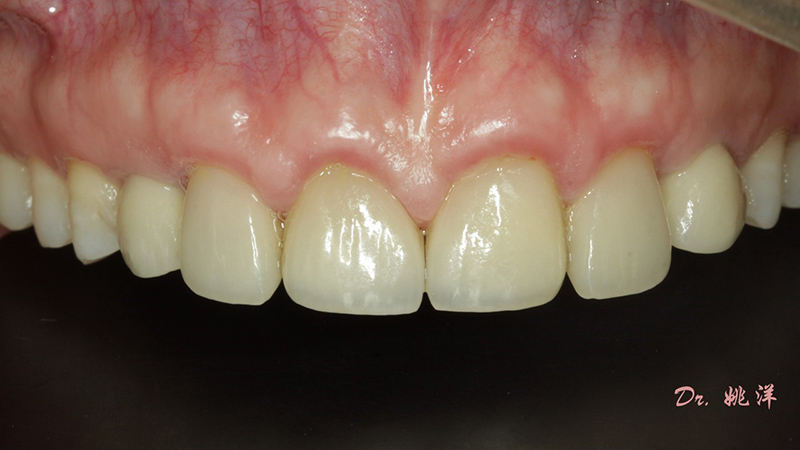

從最終修復(fù)效果可以看出:23,24間隙不足修復(fù)兩顆,修復(fù)為1顆牙。因?yàn)榻?jīng)過(guò)數(shù)字化設(shè)計(jì)和精確導(dǎo)航植入,修復(fù)體齦緣協(xié)調(diào)自然

術(shù)后照片

恢復(fù)了正常的淺覆合淺覆蓋